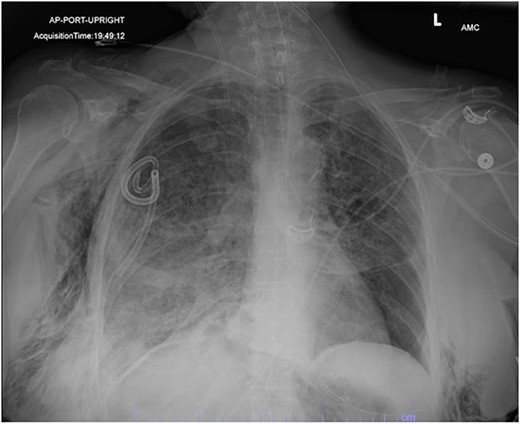

In the operating room (OR), the patient underwent intubation for TBNA using the Monarch® robotic bronchoscopy platform. Nine needle aspirations were obtained from the third-order RLL bronchi with each aliquot subjected to rapid on-site examination. While awaiting results, the patient developed retching, hemoptysis, bronchial bleeding from the superior segment of the RLL lobe and hypotension. The bleeding was managed with ice-cold saline and epinephrine. The patient required aggressive resuscitation with crystalloid, blood products and vasopressor therapy. She was transferred to the ICU where she remained intubated for ongoing resuscitation. In the ICU, the patient developed recurrent hypotension. Chest X-ray (CXR) revealed a right-sided pneumothorax (Fig. 1) that was treated with a small-bore pigtail chest tube and resulted in immediate improvement of her tension physiology. The pneumothorax resolved on repeat chest film while the patient remained intubated and sedated (Fig. 2).

AP upright chest radiograph showing placement of right-sided chest tube and resolution of right pneumothorax.